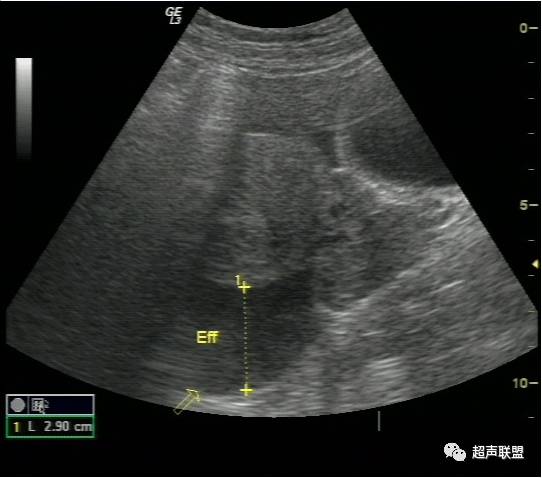

超声检查声像图特点:

(1)子宫增大或轻度增大,子宫内膜不同程度增厚,宫内未见妊娠囊。

(2)一侧附件区可探及不均质包块,包块形态欠规则,边界不清楚,回声紊乱。

(3)陶氏窝:可见多少不一不规则的液性暗区,暗区中有密集点状回声。

宫外孕破裂出血是妇产科最常见的急腹症之一。出血量大者,病情特别危急,需要立即作出诊断和鉴别诊断,以便采取适当而有效的治疗措施。对于一个临床主要表现为下腹剧痛,超声表现为:子宫轻度增大,子宫内膜不同程度增厚,宫内未见妊娠囊;一侧附件区可探及不均质包块,包块形态欠规则,边界不清楚,回声紊乱;陶氏窝可见多少不一不规则的液性暗区,暗区中有密集点状回声。盆腔甚至腹腔积液的妇产科急症患者。检查者应该想到上述疾病。并尽可能详细询问月经史、性生活史及临床病史,结合尿或血HCG检查、血常规检查等,进行综合分析判断。随着超声仪技术的发展,阴道彩色多普勒检查的应用,宫外孕包块内滋养层血流的检测,将更有助于宫外孕破裂的诊断及鉴别诊断。